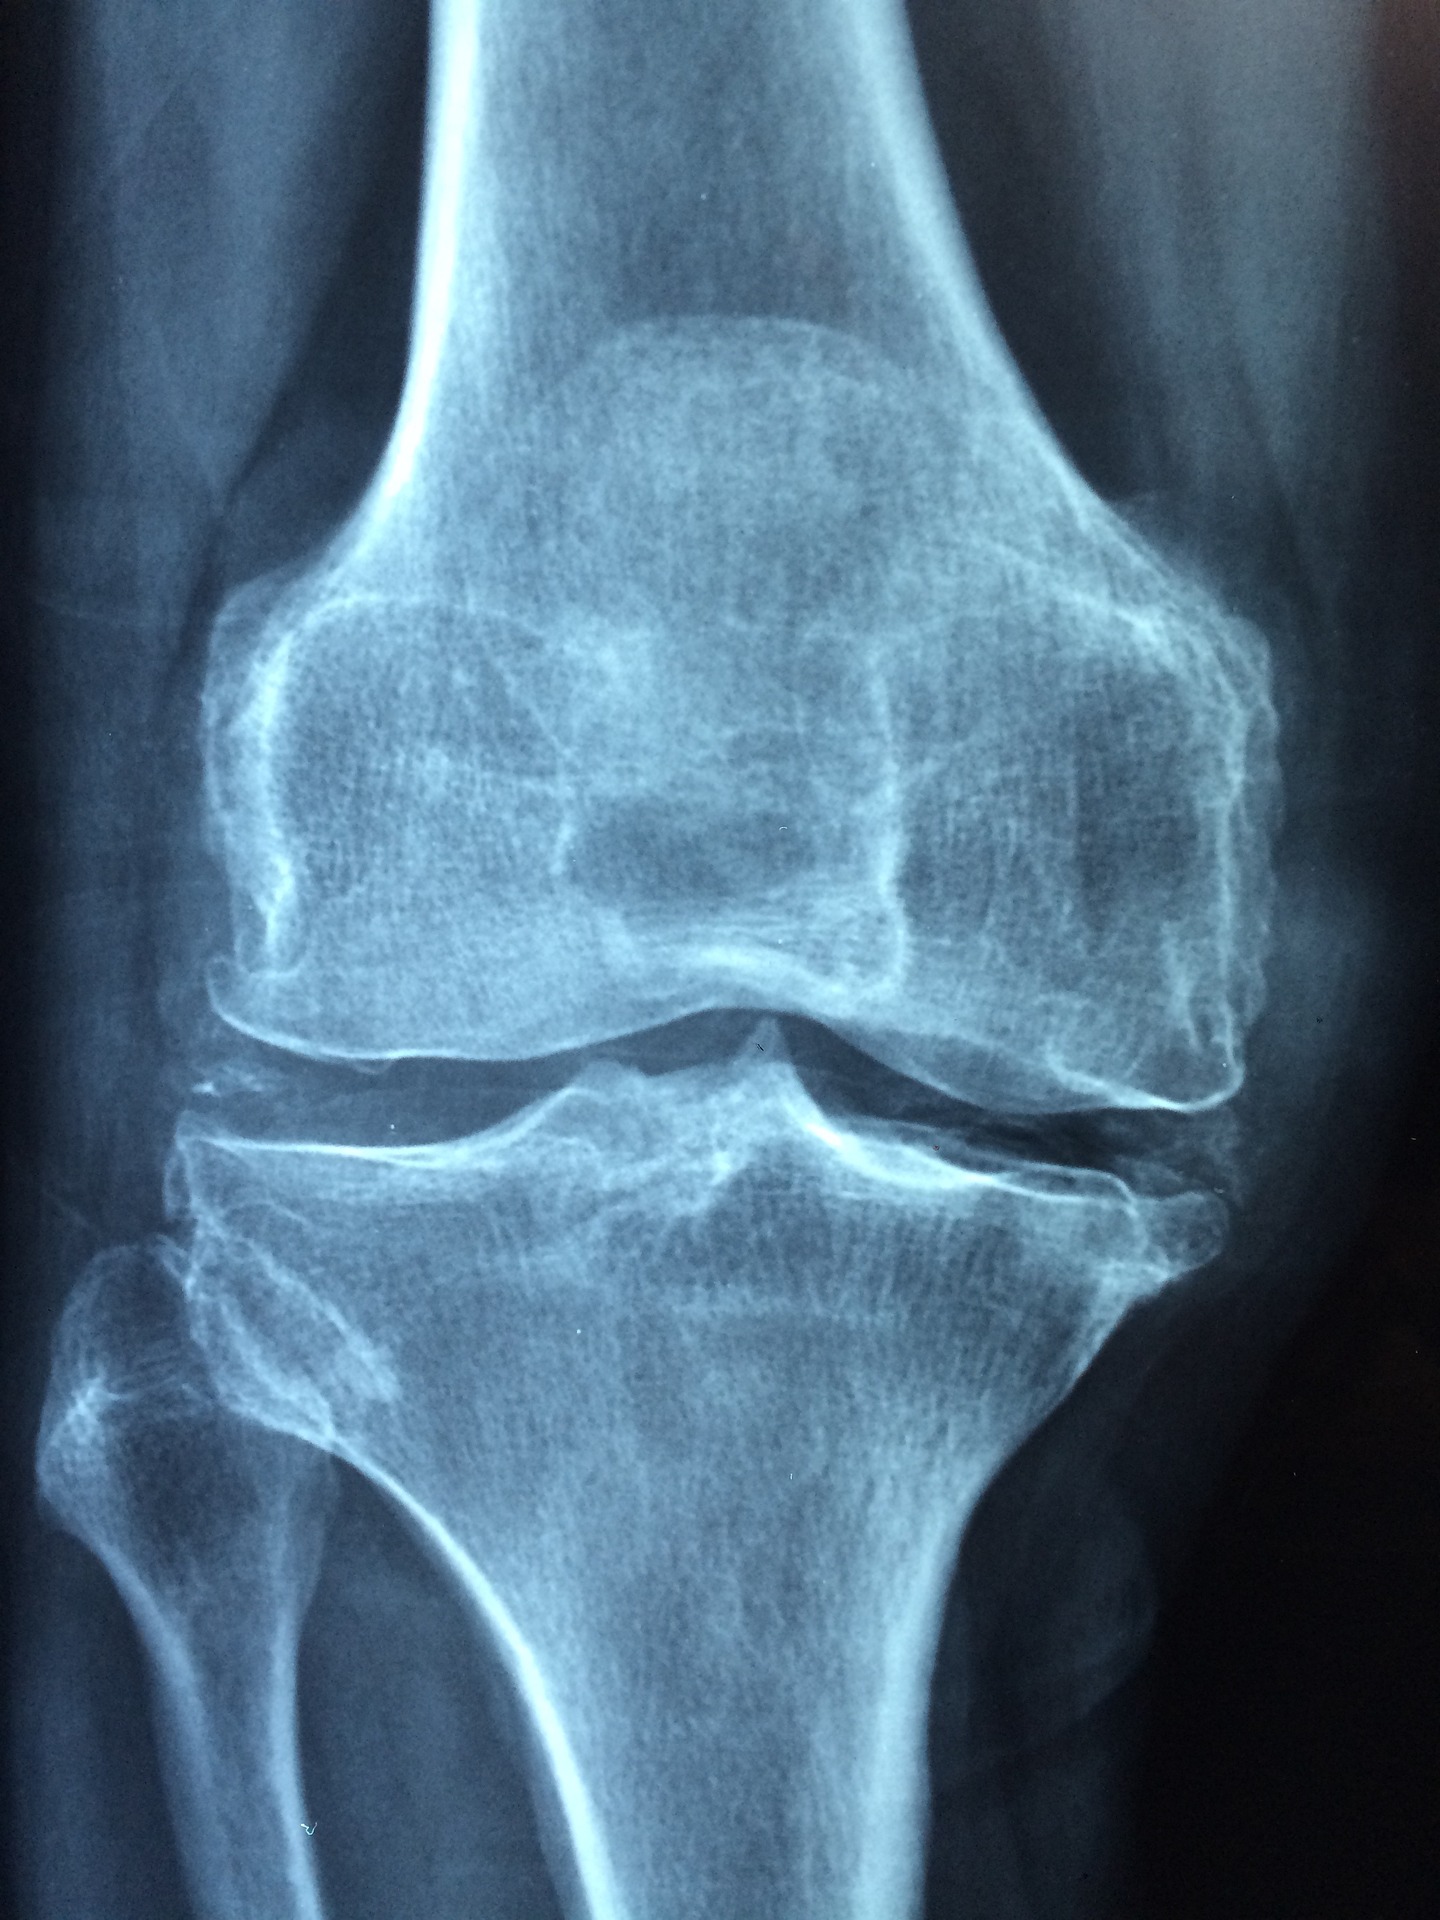

현대사회에서 골다공증에 관한 이야기를 많이 듣게 되며 골다공증으로 뼈가 쇠약해지는 증상을 맞기 위해 최선을 다해야 합니다. 우리가 움직일 수 있게 도와주는 뼈는 중요한 비중을 차지하고 있으며 뼈로 인해 일상생활이 가능할 정도로 중요한 자리를 차지합니다. 그렇다면 골다공증은 어떤 의미를 지니고 있을까요? 사전적인 의미로 골다공증은 뼈가 쇠약해지고 뼈가 잘 부러지거나 골절이 생길 수 있는 상태를 골다공증이라고 합니다. 즉 뼈가 약해지기 때문에 다양한 증상이 나타나며 이를 예방하기 위해서는 지금부터 실천하는 것이 좋습니다.

▶골다공증의 증상

골다공증은 일상생활에 불편함을 호소하기도 하는데요, 초기에는 미세한 증상으로 알기 어려울 수 있습니다. 뼈가 시리거나 아프기도 하며 몸이 통증이 발생할 수 있습니다. 하지만 골다공증을 방심한 채 지나간다면 증상이 심각해질 수 있으며 뼈가 점점 약해져 우리 몸을 지탱할 수 없고 걸어 다닐 힘조차 빠져나가게 됩니다. 따라서 골다공증을 미리 예방을 하고 주기적으로 건강검진을 받으며 자신의 몸에 이상이 없는지 체크하는 게 좋습니다.